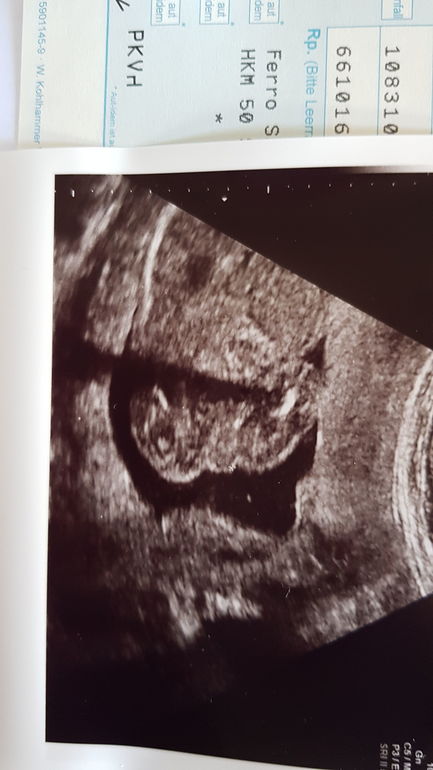

Мальчик или девочка?

Скорее девочка но видно плохо

Стручка не вижу, девочка похоже

Если это ракурс снизу, то больше похоже на девочку 🤔 А врач кого предположил?

Врач предложил и девочку и мальчика, говорит : с такого ракурса девочка с другого ракурса вообще мальчик😀. Но похоже всетаки девочка....

Мне тоже кажется, что девочка)

Подумала может у когото глаз лучше чем у моего врача😀 , она предложила и мальчика и девочка. В четвертый раз беременна, и впервые такое что врач на узи не может определится кто там.... а 20 недель уже!